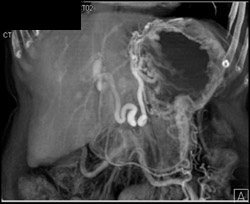

Cirrhosis With Varices